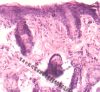

Fig. 1.

H&E stain for group 1 (seventh-day sample).